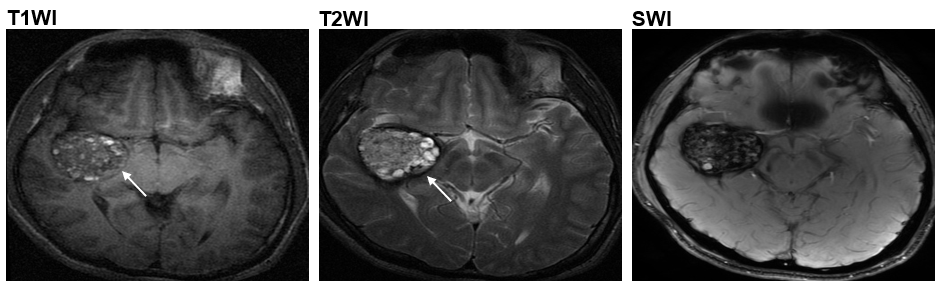

Now, using next-generation sequencing and computational approach, a research team led by Prof. WANG Jiguang, Assistant Professor from HKUST’s Division of Life Science and Department of Chemical and Biological Engineering, in collaboration with Prof. CAO Yong from the Beijing Tiantan Hospital, analyzed the genomic data of 113 CCM patients and identified another mutation called MAP3K3 c.1323C>G, which is found to be responsible for almost all the tested cases who developed popcorn-like lesions in their brain arteries - the most common one among the four types of CCM lesions1(type II CCM).

The popcorn-like lesions (as indicated by the arrows) in the brain arteries of Type II CCM patients